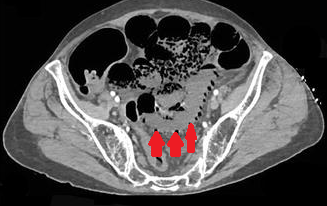

CT κοιλίας. Κόκκινο βέλος — Τυφλίτιδα. Σημαντική πάχυνση τοιχώματος τυφλού (Ευγενική παραχώρηση Dr. V. Penopoulos)